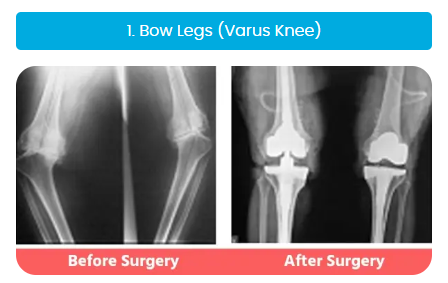

Complex Knee & Hip Replacement Surgeries

Our surgeons are highly experienced in handling complex cases like bow legs (varus), knock knees (valgus), or wind-swept legs, and have considerable expertise in revision joint replacement surgeries.